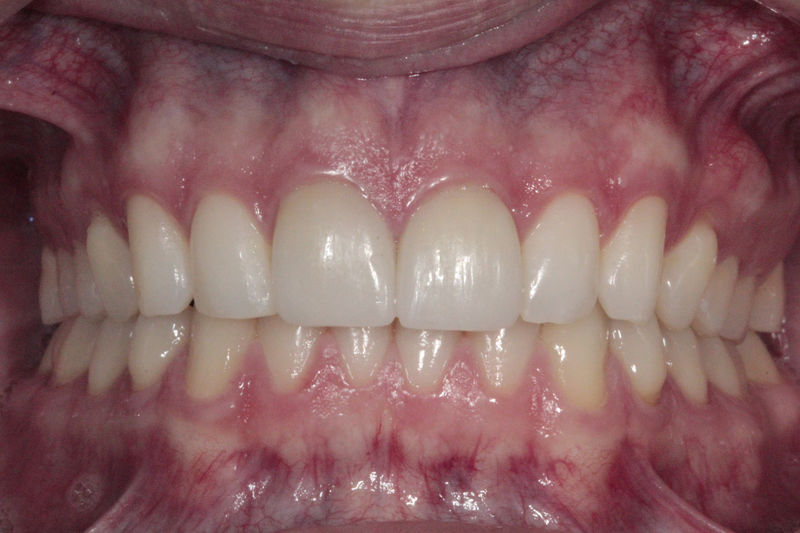

Implante fracasado, extracción, carillas, coronas y prótesis fija.